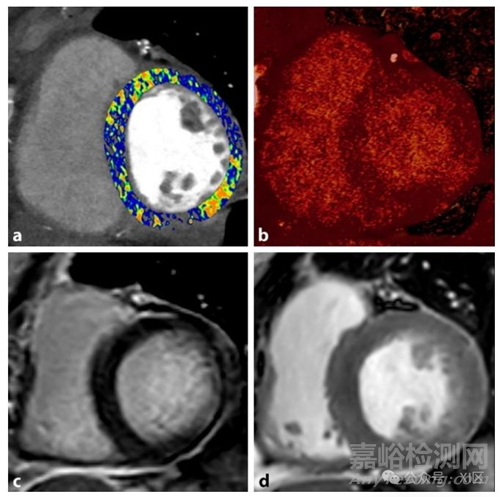

一名59歲近期被診斷為心肌梗死的女性的短軸位PCD-CT(圖a和圖b)和心血管磁共振圖像(圖c和圖d)。圖a展示了左心室的PCD-CT細(xì)胞外容積(ECV)圖,基底部下外側(cè)段ECV局灶性增加。圖b顯示了計(jì)算得到的碘圖,碘呈缺血性分布模式潴留,與心血管磁共振上的延遲釓增強(qiáng)區(qū)域(圖c)相對(duì)應(yīng)。圖d為(注射釓劑后的)短軸位電影圖像,其中基底部下外側(cè)段觀察到信號(hào)強(qiáng)度增加和節(jié)段性室壁運(yùn)動(dòng)異常,提示心肌梗死。